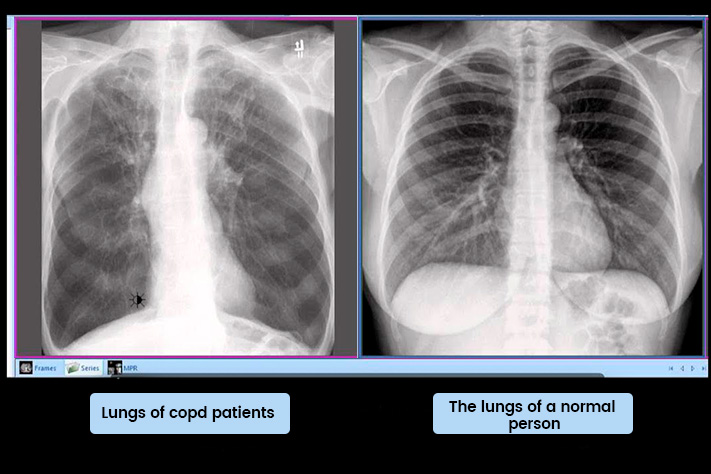

There's a hidden problem affecting 87% of COPD patients right now.

It's causing them to slowly suffocate while their Mucinex sits useless in the bathroom cabinet.

And here's the part that makes pulmonologists furious: The very treatments you've been told to use can't reach where the real problem lives.

I'm talking about what respiratory researchers now call "the suffocation layer"-but patients describe it more simply: the mucus trap.

It's something stuck deep in your lungs that gets worse every single day you don't address it. The reason you wake up choking. The reason you can't sleep flat. The reason three years of Mucinex hasn't changed anything.

"Because most doctors don't know to look for it. We can't see it on X-rays. We keep prescribing treatments that only work on the surface."